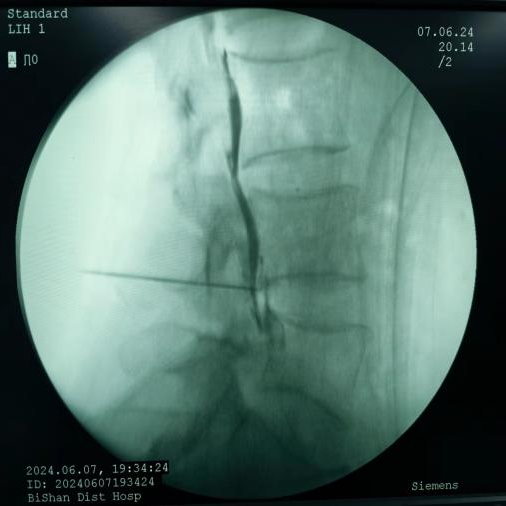

鞘内泵植入术:将药物输注导管植入鞘内,通过体外或体内泵持续输入镇痛药物,作用于中枢阿片受体,治疗癌痛及顽固性疼痛。

鞘内泵植入术